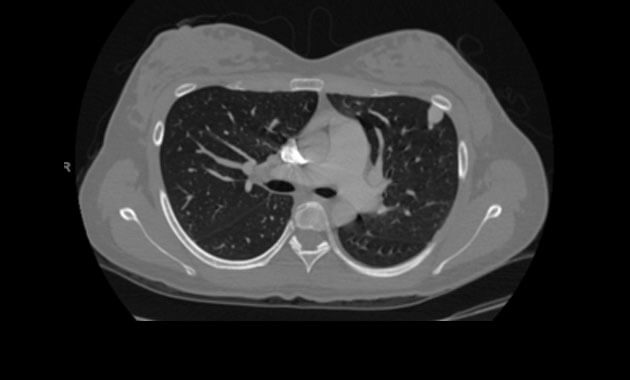

A chest CT scan may also be performed to evaluate for PAVMs. It is also highly sensitive for detection of pulmonary AVMs, but it involves radiation exposure. For this reason, a chest CT is usually reserved for those patients with known PAVMs or a positive echocardiogram with bubble study to determine if treatment is necessary and to determine the anatomy of the AVM and treatment options.

Chest CT depicting

Pulmonary Arteriovenous Malformations (PAVMs).